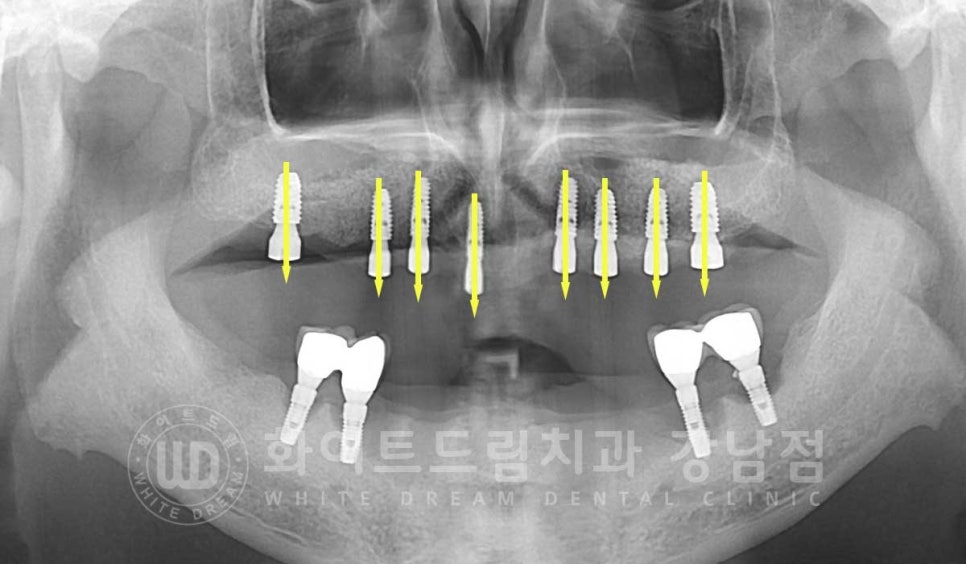

상악부터 알아보겠습니다.

상악은 오랜 시간 치아가 없는 상태여서 상악동이 하방으로 커진 상악동함기화가 발생한

상태였고, 골흡수도 동반되어 임플란트를 식립하기에 안정적인 만큼의 잇몸뼈가 없는 상태였습니다.

상악 어금니 부위는 저작력이 강한 부분으로 임플란트

보통 길이 7-10mm의 임플란트를 식립합니다.

이 정도의 임플란트가 식립되기에는 잇몸뼈의 길이 모자란 상태여서

상악동 거상술을 동반한 뼈이식을 함께 진행한 후 임플란트 식립을 진행하기로 했습니다.

▲ 상악동 거상술을 동반한 임플란트 식립 후

하악은

하악의 부분틀니의 지대치로 사용하고 있던 임플란트 4개 주위에 모두 염증이 발생했고

이로 인해 임플란트가 심하게 흔들리고, 주위 골소실도 있는 상태였습니다.

전체 임플란트 치료를 받고자 하셨기에

염증 제거 후 임플란트 재식립을 진행하기로 치료 계획을 세웠습니다.